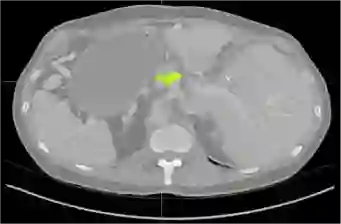

Creating large-scale and well-annotated datasets to train AI algorithms is crucial for automated tumor detection and localization. However, with limited resources, it is challenging to determine the best type of annotations when annotating massive amounts of unlabeled data. To address this issue, we focus on polyps in colonoscopy videos and pancreatic tumors in abdominal CT scans; both applications require significant effort and time for pixel-wise annotation due to the high dimensional nature of the data, involving either temporary or spatial dimensions. In this paper, we develop a new annotation strategy, termed Drag&Drop, which simplifies the annotation process to drag and drop. This annotation strategy is more efficient, particularly for temporal and volumetric imaging, than other types of weak annotations, such as per-pixel, bounding boxes, scribbles, ellipses, and points. Furthermore, to exploit our Drag&Drop annotations, we develop a novel weakly supervised learning method based on the watershed algorithm. Experimental results show that our method achieves better detection and localization performance than alternative weak annotations and, more importantly, achieves similar performance to that trained on detailed per-pixel annotations. Interestingly, we find that, with limited resources, allocating weak annotations from a diverse patient population can foster models more robust to unseen images than allocating per-pixel annotations for a small set of images. In summary, this research proposes an efficient annotation strategy for tumor detection and localization that is less accurate than per-pixel annotations but useful for creating large-scale datasets for screening tumors in various medical modalities.